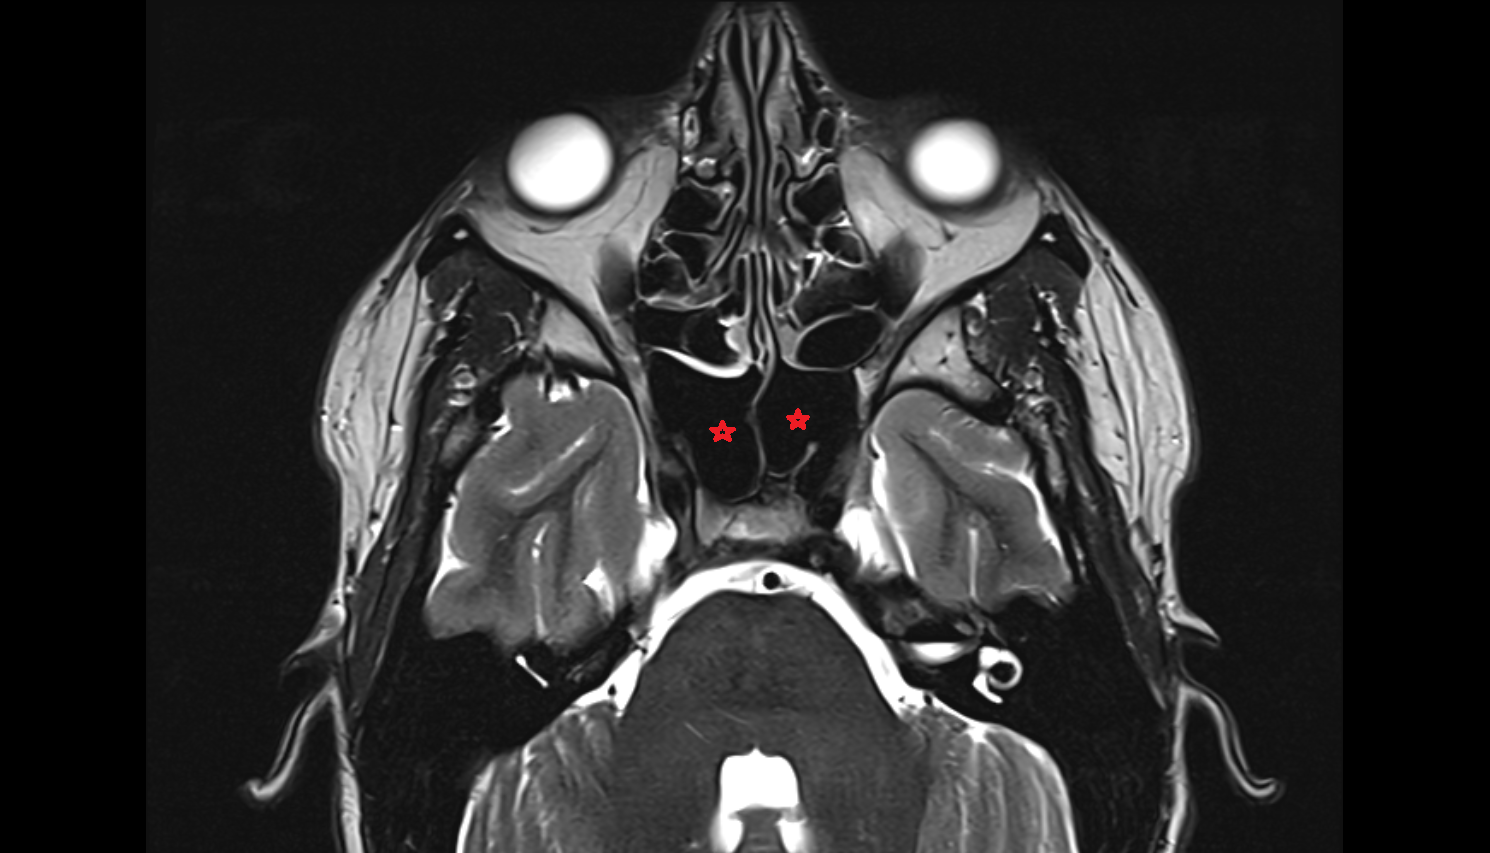

- Meckel’s cave (Trigeminal cave)